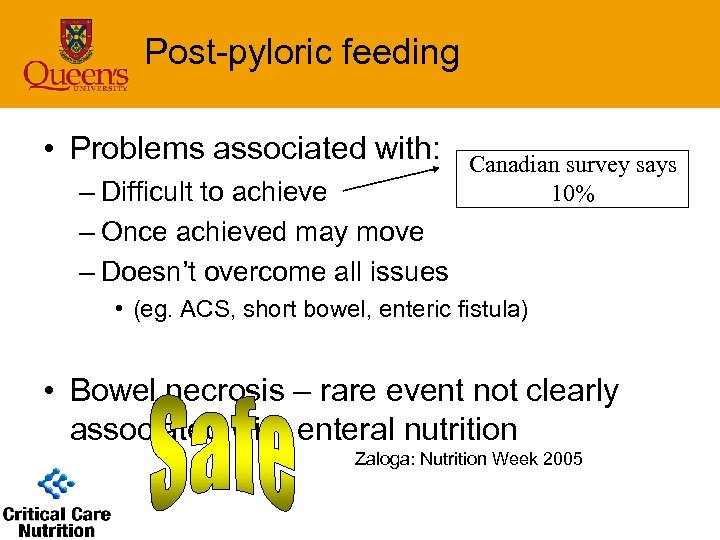

Post-pyloric feeding • Problems associated with: – Difficult to achieve – Once achieved may move – Doesn’t overcome all issues Canadian survey says 10% • (eg. ACS, short bowel, enteric fistula) • Bowel necrosis – rare event not clearly associated with enteral nutrition Zaloga: Nutrition Week 2005

Post-pyloric feeding • Problems associated with: – Difficult to achieve – Once achieved may move – Doesn’t overcome all issues Canadian survey says 10% • (eg. ACS, short bowel, enteric fistula) • Bowel necrosis – rare event not clearly associated with enteral nutrition Zaloga: Nutrition Week 2005